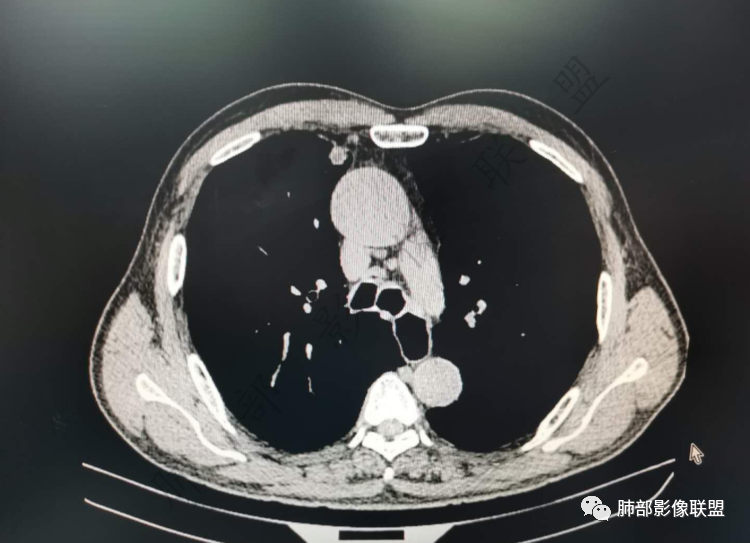

右肺上类圆形叶结节,周边见细软毛刺,增强后呈环形明显强化,内部坏死,邻近胸膜光滑,结合病史2个月明显增大,考虑炎性可能性大。

老年男性,炎性指标略高,肺气肿背景。右肺上叶胸膜下结节,部分边缘平直,部分稍膨隆,供血血管增粗,增强扫描病灶中心密度减低,呈环形强化,邻近脂肪间隙清晰。考虑炎性肉芽肿或慢性炎症,鉴别鳞癌。

右肺上叶前段胸膜下结节,边缘分叶毛刺,血管集束,支气管截断,纵膈胸膜牵拉,内乳动脉增粗,密度不均,中央可见坏死,两个月短期随访结节有增大,考虑恶性,腺癌。鉴别结核。

肺气肿背景,右肺上叶纵隔旁胸膜下结节,有血管集束,支气管堵塞,内乳动脉增粗,增强不均匀强化,内可见低密度区。考虑为恶性可能性大

老年男性,肺气肿背景,右肺上叶胸膜下弧立实性不规则结节,密度不均,其内低密度坏死影,支气管似有截断,血管集束,2月复查明显增大,考虑恶性,鳞癌可能大,鉴别炎性肉芽肿

老年男性,炎性指标略高。影像表现右肺上叶胸膜下结节,膨胀性生长部分边缘平直,边界清晰,病灶可见血管集束征,近段支气管阻断?增强扫描病灶中心密度减低,低密度区边界模糊,外围环形强化。老年性,不能排除恶性病变,周围性鳞癌,其次才考虑炎性肉芽肿或慢性炎症

右肺上叶前段胸膜下结节,近段支气管截断,血管伸入结节内,密度不均,同侧临近内乳动脉增粗,不均匀强化,肺气肿背景,两月明显增大,考虑低分化鳞癌,隐球菌代排

老年男性,白细胞计数及CRP稍高,右肺上叶结节,两个月来有增大,部分边缘可见边界模糊的GGO,局部边缘平直、凹陷,临近胸膜增厚,内见坏死,坏死区边界未见明显壁结节,壁较厚而且均匀强化,支气管似乎有扩张然后截断,近端血管增粗明显。考虑炎性病变,脓肿?有结核病人密切接触史,注意是否为结核。有点难以理解的是为什么右侧内乳动脉增粗明显。

老年男性,无症状,炎性指标增高。肺气肿背景,右肺上叶前段结节,边缘部分平直部分澎隆,血管集束,支气管至病变边缘似截断,近端扩张。增强环形强化,中心坏死。两月内病灶增长太快,考虑炎性肉芽肿,慢性脓肿?结核?癌待排。